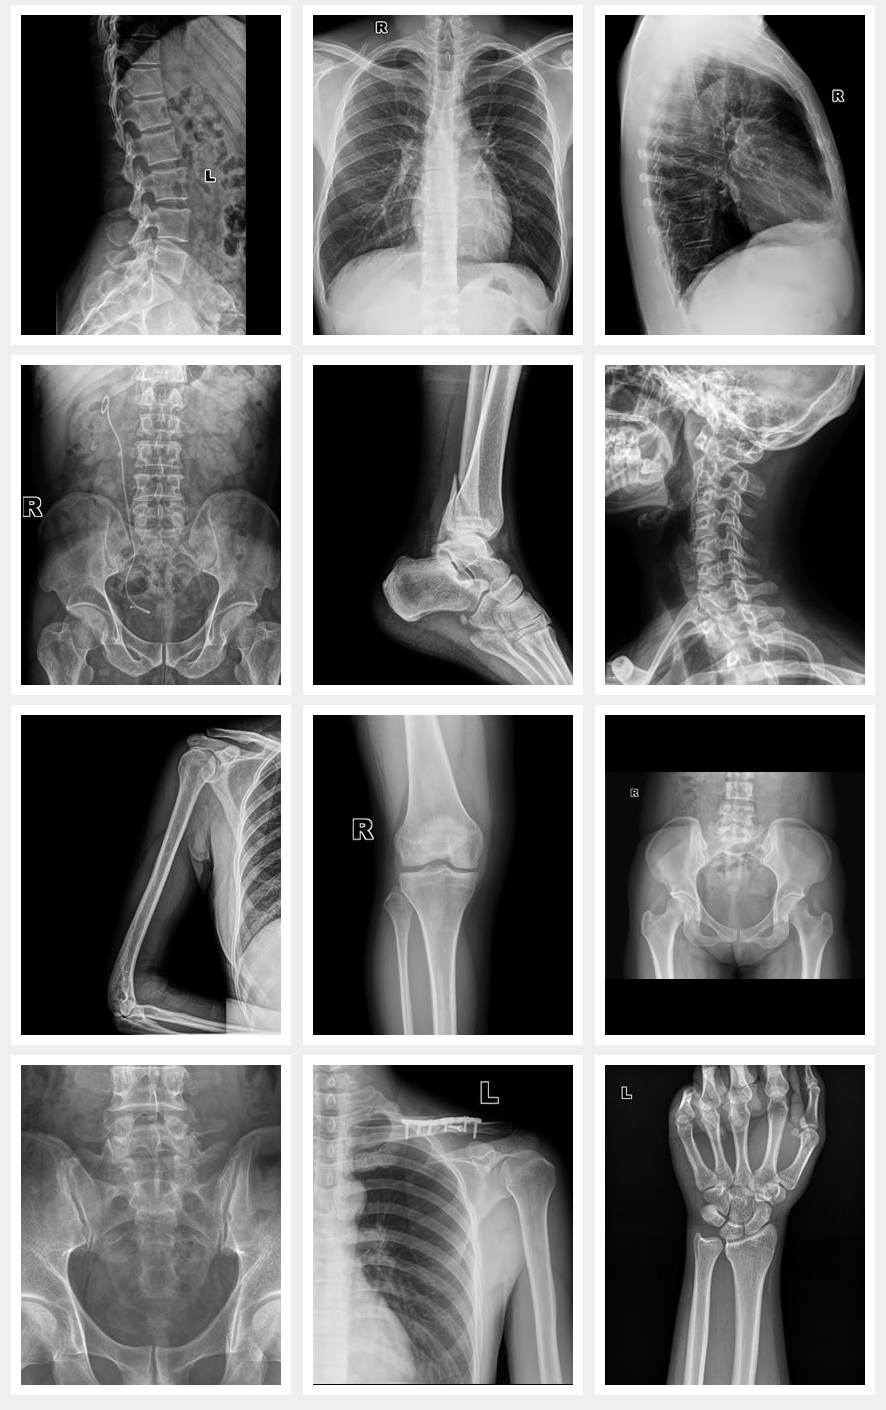

Applications

Images cliniques